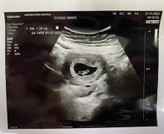

9 วีคค่ะ..เพิ่งไปมาวันนี้ ชัดเจนเลยค่ะ..ถ้าไปตอน 4-5 วีค เวลาอัลตร้าซาวน์อาจจะยังไม่เห็นน้อง

หน้าท้องค่ะ